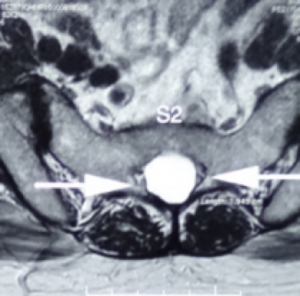

骶管襄腫一般生長於骶骨的第一節至第三節,內裹充滿了腦脊液, 襄腫可逐漸增大導致馬尾神經線被壓迫, 引起神經根發炎或產生脊髓病變及令骨性結構也被侵入破壞.。磁力共振檢查可清楚分辨骶管襄腫的位置,大小及與硬脊膜和神經根的關係。

一般細小的骶管襄腫多數不會引起任何問題.但如病人的徵狀引起神經缺損而嚴重地影響日常生活, 手術介入可能是最好的選擇。 手術經腦神經外科醫生處理,以微創手術,將襄腫抽吸腦脊液,再封堵阻止脊液進入,然後拿取病人身體的脂肪或肌肉來填塞襄腫空間。( 圖ー , 圖ニ)